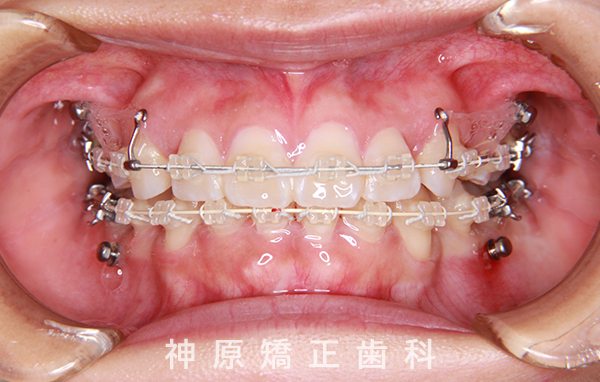

マルチブラケット装着1年後

口元の突出感と下の歯並びの乱れを改善するため、小臼歯を抜歯することにしました。抜いたスペースを利用して、前歯をできるだけ後ろに移動させるため、上下に歯科矯正用アンカースクリューを使用する計画を立てました。治療の目標について同意を得た後、矯正治療を開始しました。歯の動きが順調で、1年9カ月で治療が完了しました。その結果、側貌はE-lineに調和したバランスの良い仕上がりになりました。